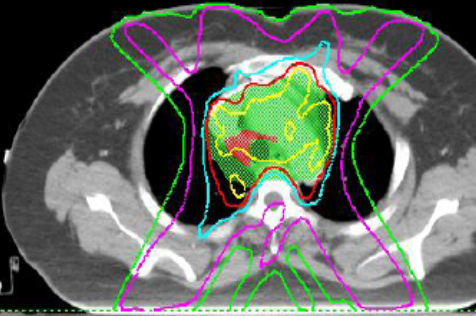

典型RILI影像表现及射野

WUj2fvhRjYOMcNYU.jpg EUuSa662a6s4XYS0.jpg